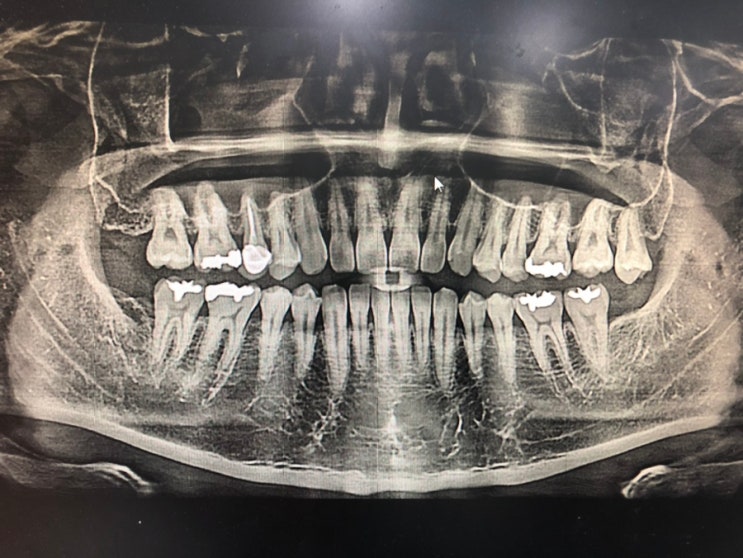

치과

지난달의 일이었다. 정기적인 엑스선 촬영에서 발견된 문제를 해결해야 했다. 충치였다. 십여 년 만의 충치...